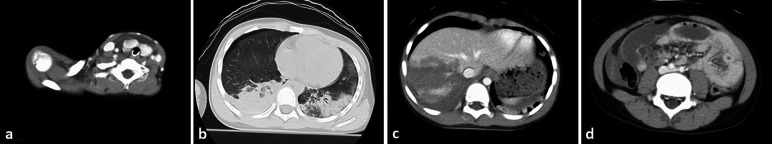

FAST revealed fluid collection in the bladder, ischio-rectal fossa, and Morrison's fossa, which was suggestive of intra-abdominal hemorrhage. Contrast-enhanced computed tomography (CT) performed 17 min after admission with rapid intubation in the emergency room showed thyroid injury, bilateral hemopneumothorax and pulmonary contusion, and grade IV right hepatic lobe parenchymal injury [5] (Fig. 1a–c). Although there was no obvious free air, some intestinal dilatation was observed, suggestive of intestinal injury (Fig. 1d). No significant extravasation from the hepatic artery was observed. At this time, the patient’s serum hemoglobin level was 9.6 g/dL and his prothrombin time-international normalized ratio was 1.25 (Table 1). Red blood cells (RBCs) and fresh frozen plasma (FFP) were transfused. His hemodynamic condition stabilized with fluid resuscitation and blood transfusion. He had acidosis (pH 7.338) and a bicarbonate level of 19.9 mmol/L, base excess of − 4.9 mmol/L, and lactate level of 24 mmol/L. Although his hemodynamic condition was stable, the patient’s altered level of consciousness, the presence of signs of peritoneal irritation, and suspicion of intestinal injury led us to perform exploratory laparotomy. After thoracic cavity drains were placed bilaterally for treating the hemopneumothorax, the patient was transferred to the operating room 57 min after admission. On opening the abdomen, there was spillage of a large amount of hemorrhagic ascites fluid. A laceration was noted in the right lobe of the liver, and no intestinal injury was observed. As part of a DC strategy, we packed the right lobe of the liver from the ventral and dorsal sides using gauze. We covered the abdomen with an ABTHERA Open Abdomen Negative Pressure Therapy System (Fig. 2). The operative time was 23 min, total blood loss was 1185 mL, and total amount of blood transfused intraoperatively and preoperatively was 1120 mL of RBCs (eight units) and 240 mL of FFP (two units). The hemorrhage was gradually controlled with direct gauze packing. The anemia and coagulopathy improved; his serum hemoglobin level was 11.5 g/dL, prothrombin time was 14.3 s, and fibrinogen level was 304 mg/dL at 4 h after surgery.

Fig. 1.

a–d Preoperative contrast-enhanced computed tomography images. Axial view shows irregularity and fluid collection around the thyroid gland, bilateral hemopneumothorax and pulmonary contusion, faint contrast effect with a band on the right lobe of the liver, and localized dilatation of the small intestine in multiple locations